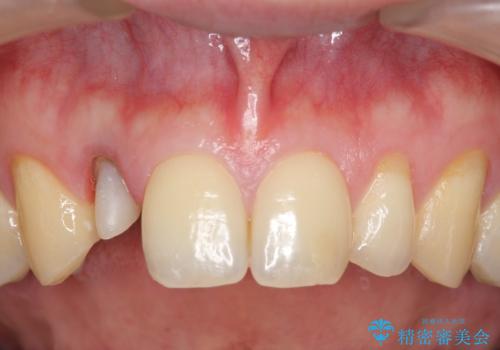

- 金属を使っていない被せ物に替えたいといらっしゃった方の症例です。

再根管治療終了後、オールセラミッククラウンによる補綴を行いました。